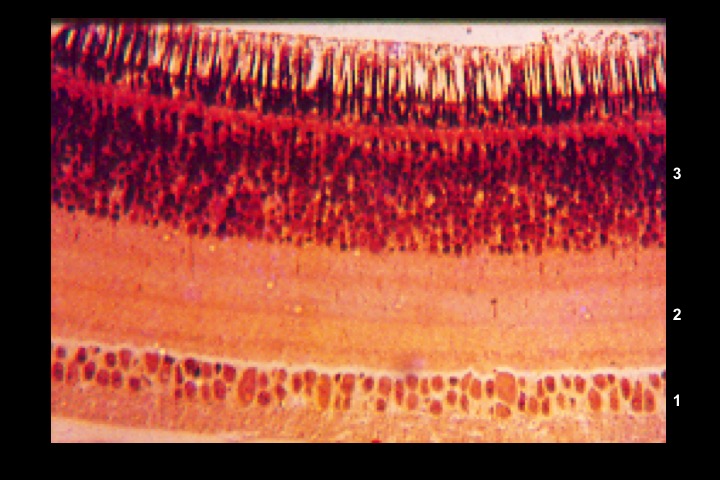

Corte histológico da retina de galinha